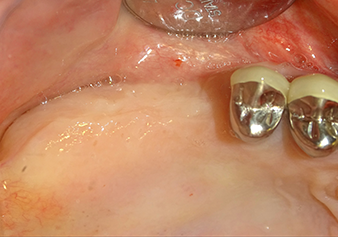

A 49-year-old female patient, a non-smoker and with nothing remarkable in her general medical history, was referred to our oral surgery practice for surgical extraction of tooth 16 and subsequent implantation. After the extraction, the patient experienced mild sinusitis trouble with the resultthat we initially waited six months before carrying out the measure. The residual bone height at the planned implant position measured 3-4 mm (Fig. 1 and 2).